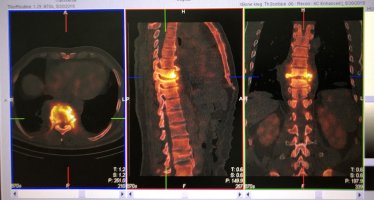

Przykładowe obrazy scyntygraficzne uzyskiwane w naszym Zakładzie Medycyny Nuklearnej: